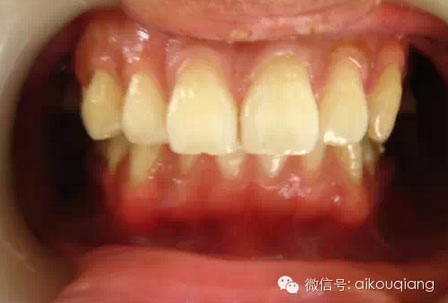

洗牙(潔治)后效果很明顯